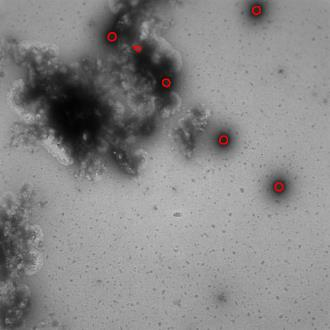

Regular monitoring of the primary particles and purity profiles of a drug product during development and manufacturing processes is essential for manufacturers to avoid product variability and contamination. Transmission electron microscopy (TEM) imaging helps manufacturers predict how changes affect particle characteristics and purity for virus-based gene therapy vector products and intermediates. Since intact particles can characterize efficacious products, it is beneficial to automate the detection of intact adenovirus against a non-intact-viral background mixed with debris, broken, and artefact particles. In the presence of such particles, detecting intact adenoviruses becomes more challenging. To overcome the challenge, due to such a presence, we developed a software tool for semi-automatic annotation and segmentation of adenoviruses and a software tool for automatic segmentation and detection of intact adenoviruses in TEM imaging systems. The developed semi-automatic tool exploited conventional image analysis techniques while the automatic tool was built based on convolutional neural networks and image analysis techniques. Our quantitative and qualitative evaluations showed outstanding true positive detection rates compared to false positive and negative rates where adenoviruses were nicely detected without mistaking them for real debris, broken adenoviruses, and/or staining artefacts.